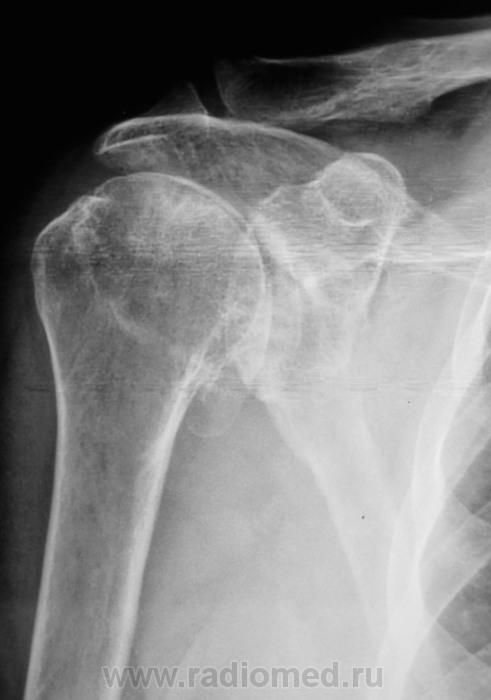

Жалобы на длительные боли в плечевом суставе

Таков артроз.

Смущает дополнительный "контур" по стрелкам.

Думаю,что это "неодокостеневшие" костные разрастания(не знаю,как точно обозвать).

ДОА.

Что в анамнезе? Была травма? После чего боли появились. Что можно сказать об объёме движений? Мне кажется, что изменения связаны с обызвествлением суставной сумки.

Боли в течение последних двух - трёх лет. Четко (при разговоре) травму вспомнить не может, хотя жительница сельской местности, где травмой считается, ну минимум перелом.

Мне кажется, что изменения связаны с обызвествлением суставной сумки.

Мне тоже так показалось.